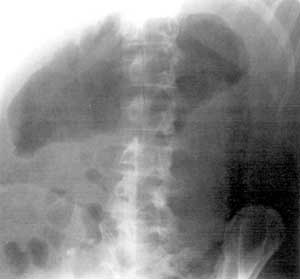

Неспецифический язвенный колит.

Рис. 9. Осложнение - токсический мегаколон.